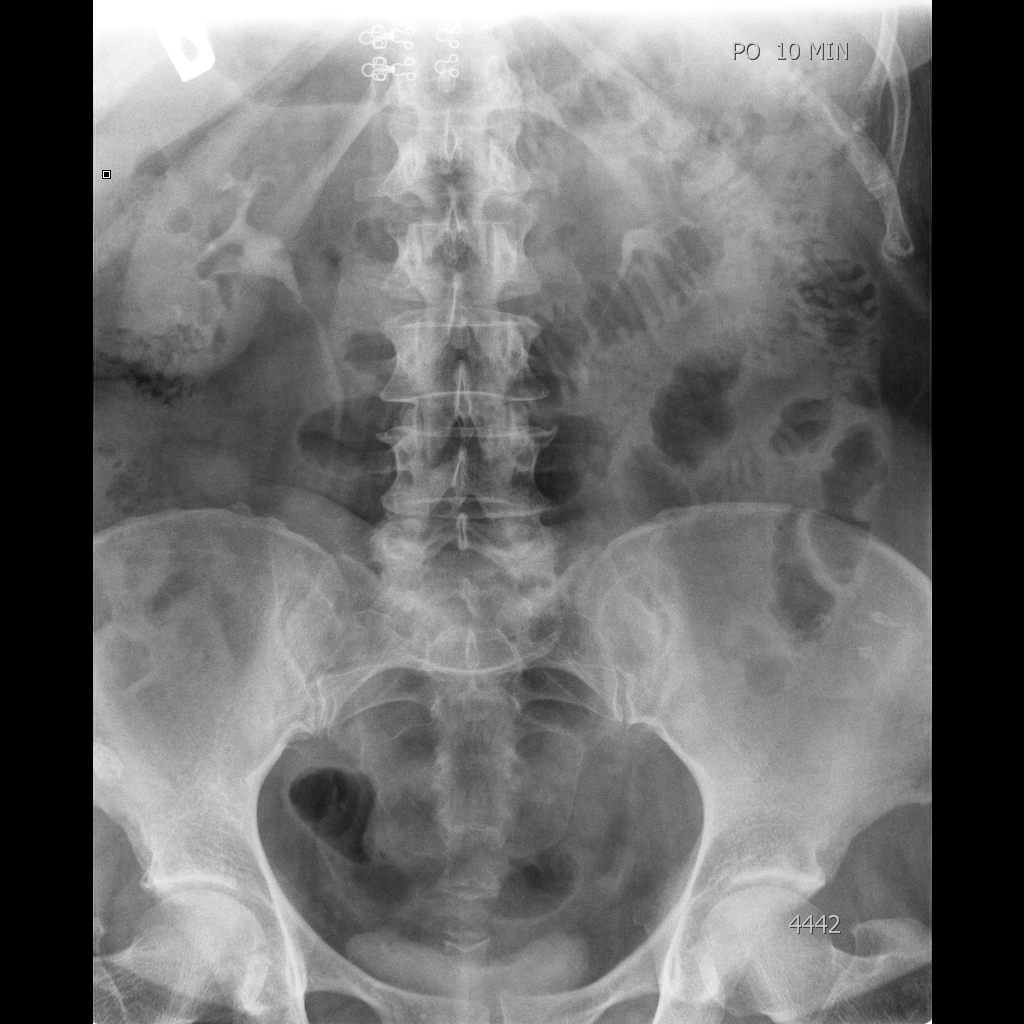

10 мин

Для меня яснее не стало - делал бы отсроченные урограммы.

Киста имхо очевидна. Без связи с чашкой.